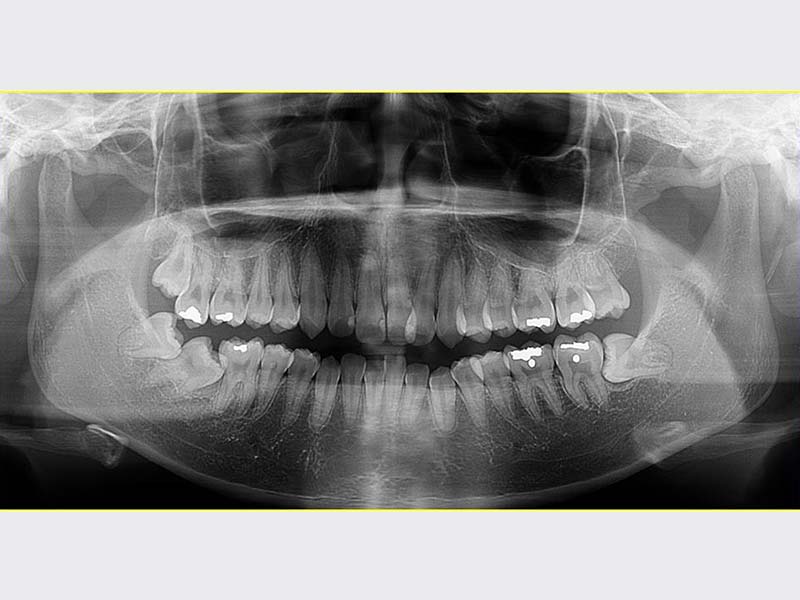

智齒手術

• 智齒手術